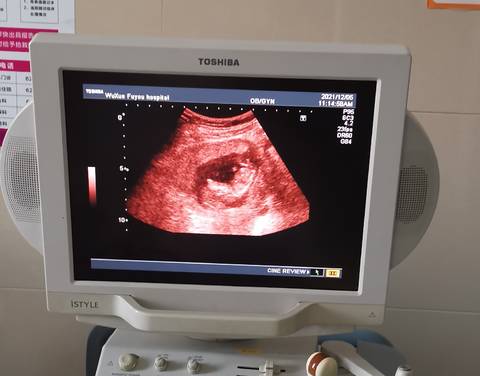

nt能看出男孩女孩吗,为啥我感觉宝宝在肚子里空间很小的感觉一样

journal_insert_pic_1674598940journal_insert_pic_1674598971